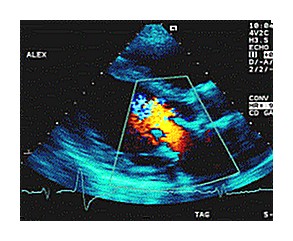

Farbkodierte Echokardiografie

So können die Herzwanddicken, die Beweglichkeit des Herzmuskels und des Klappenapparates sowie mittels Farbkodierung auch Blutströmungen und Druckverhältnisse beurteilt werden.

Herzleistungsschwäche, Herzinfarktlokalisation, Ausmaß von Klappenschäden, Ursache von Herzgeräuschen usw. können so mit hoher Verlässlichkeit beurteilt werden.